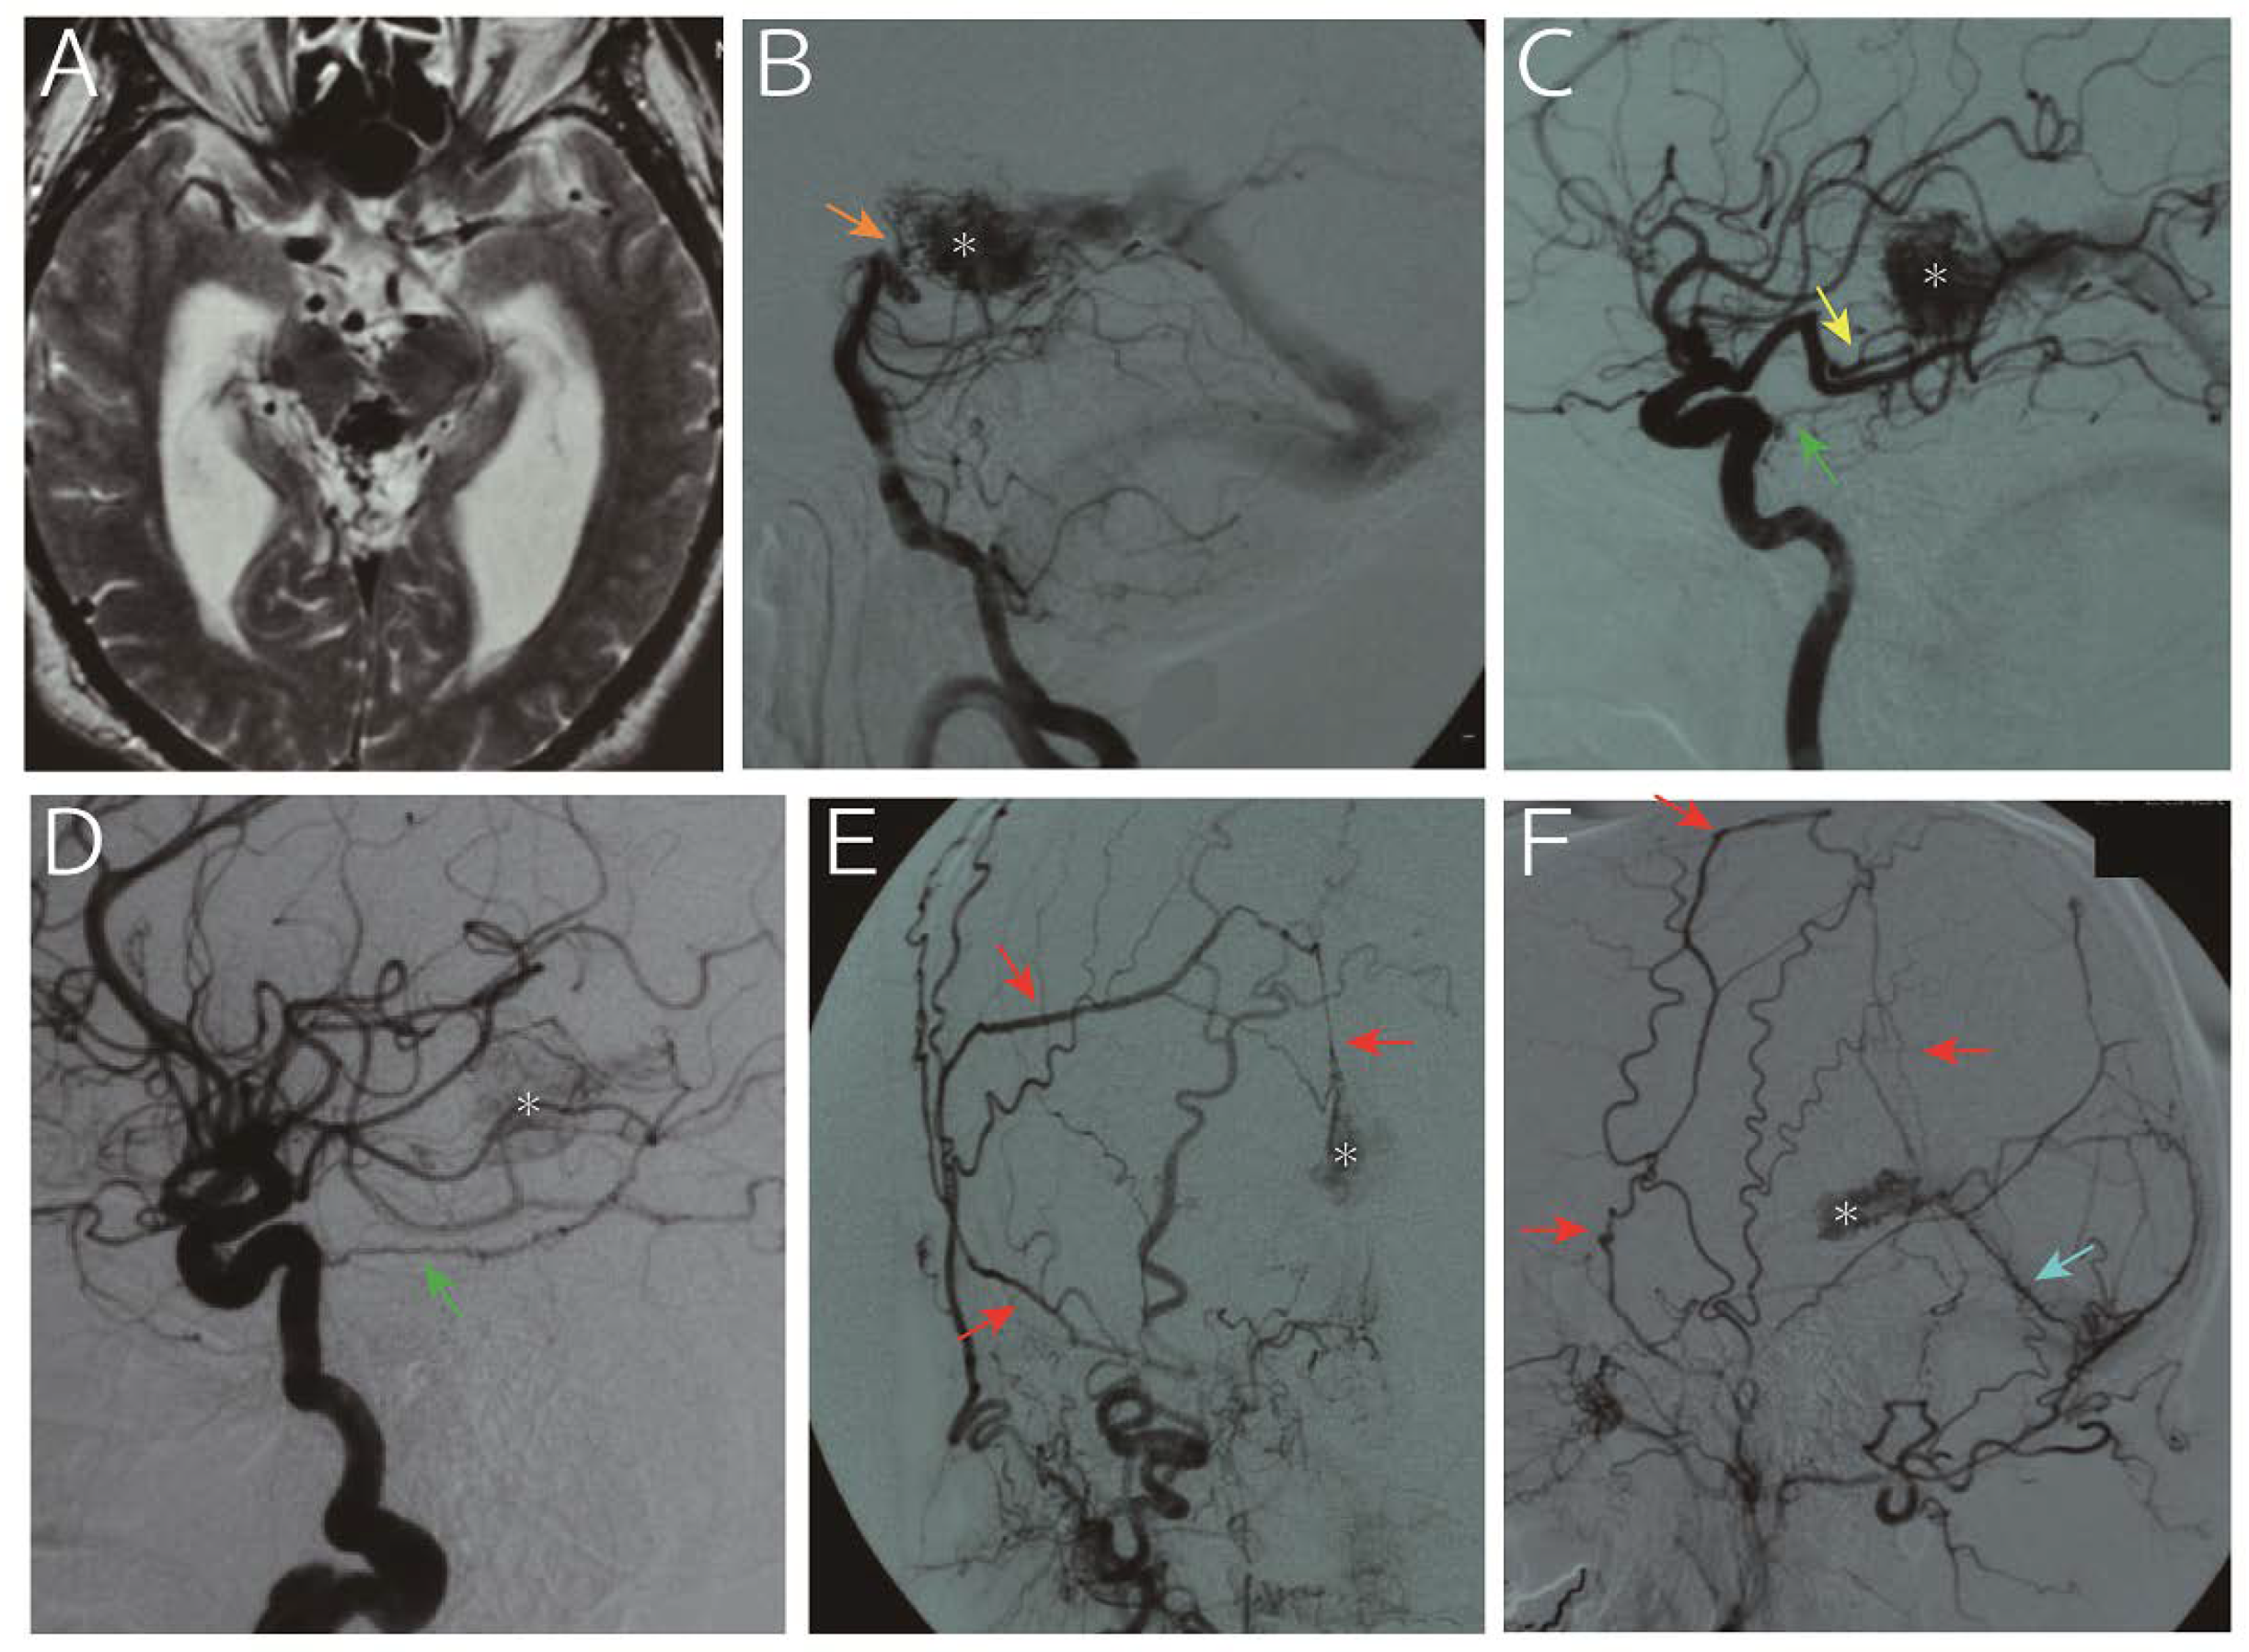

| 1 | 65, M | Hydrocephalus | 9.4 mL | MPChA, BA perforators | Tentorial a., MMA, PMA | VG | 153 mo | Died due to hemorrhage |

| 2 | 62, M | Seizure | 1.4 mL | MPChA, PCA perforators, pericallosal a. | Tentorial a. | VG | 255 mo | Alive, nidus obliteration |

| 3 | 68, M | Hydrocephalus | 0.9 mL | MPChA, PCA perforators | N/A | VG | 137 mo | Alive, nidus shrinkage |

| 4 | 31, F | Hydrocephalus and hemorrhage † | 12.2 mL | MPChA, PCA perforators | Tentorial a (N/A for the other ECA feeders) | VG | 38 mo | Alive, nidus shrinkage |

| 5 | 63, F | Headache | 2.3 mL | MPChA, PCA perforators, BA perforators | Tentorial a, MMA, PMA | VG | 47 mo | Alive, nidus shrinkage |

| 6 | 62, M | Hemorrhage | 1.2 mL | MPChA, BA perforators | Tentorial a, ILT | VG, superior vermian vein | 23 mo | Alive, nidus shrinkage |

| 7 | 55, M | Hemorrhage from flow-related AN | 1.6 mL | MPChA, pericallosal a. | ILT, PMA | VG, superior vermian vein | 12 mo | Alive, nidus shrinkage |

| 8 | 76, M | Hemorrhage | 1.7 mL | MPChA, PCA perforators | Tentorial a. | VG | 4 mo | Alive |